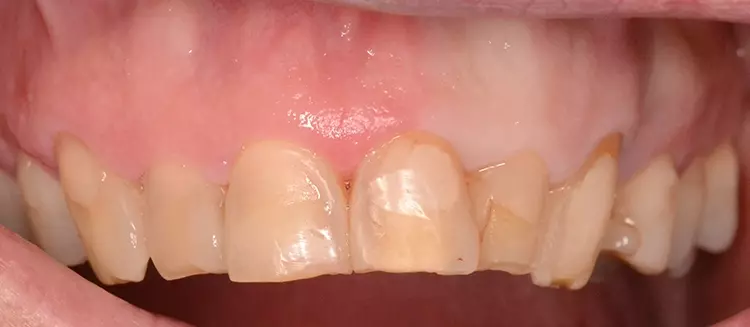

Bei dem heute 49-jährigen Patienten wurde seit Kindertagen versäumt, die Ober- und Unterkieferzahnbögen kieferorthopädisch auszurichten. Der Patient leidet seitdem stark unter seinen Zahnfehlstellungen.

Die Fraktur des stark elongierten Zahnes 21 war für den Patienten der Ausgangspunkt, sowohl die Front des Ober- als auch des Unterkiefers prothetisch überarbeiten zu lassen. Dabei wurde der frakturierte Zahn 21 durch ein navigiert eingesetztes Sofortimplantat ersetzt, während die verschachtelt stehenden Zähne 12 und 42 durch eine Brückenversorgung korrigiert wurden (Abb. 4a-j).